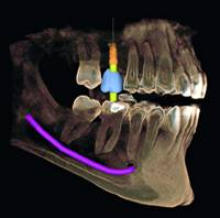

Für den Zahnarzt haben Röntgenaufnahmen einen unverzichtbaren Stellenwert in der Diagnostik und Behandlungsplanung. Für die Implantologie und viele andere zahnärztliche Bereiche bietet das digitale Röntgen eine optimale Möglichkeit der Vorplanung und Unterstützung während der Behandlung. Digitale 2D-Röntgenbilder und DVT´s/ 3D-Röntgenbilder können wir in besonders hoher digitaler Qualität und geringer Strahlendosis durchführen.

Anwendungsgebiete für die 3D-Diagnostik in unserer

Zahnarztpraxis Celle sind:

Implantologie Endodontie spezielle Parodontologie Chirurgie Zahnersatz Kieferorthopädie